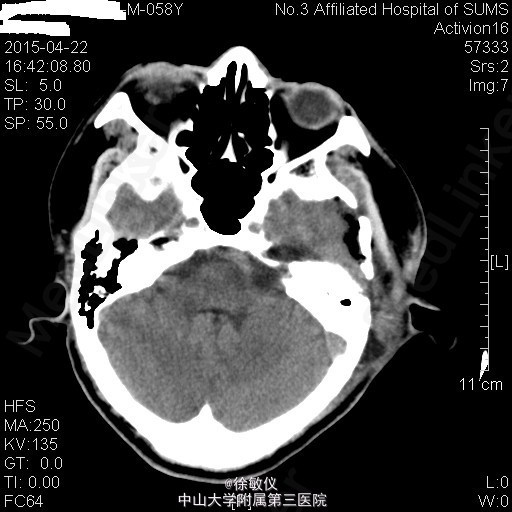

查体:左耳听力缺失,右耳听力正常。余查体无特殊。 辅查:头部MR:1、左侧桥小脑角区占位病变,考虑为听神经瘤并出血、囊变,病变与左侧听神经、椎动脉关系密切;2、颅脑MRA示脑动脉未见异常。 头部CT:双侧额顶枕叶、半卵圆中心、侧脑室周围、放射冠、基底节区及右侧岛叶多发密度灶,考虑缺血变性灶;颅脑CTA示肿瘤与左侧椎动脉关系密切。

排除手术禁忌后于2015-04-03在全麻下行左侧桥小脑角区占位病变+脑室侧引流+颅内压探头植入术,术程顺利。术后于SICU监护生命体征平稳后转入我科,予预防感染、抑酸、营养支持及对症治疗,患者恢复良好。 术后复查头部CT未见明显异常。 病理诊断:(桥小脑角占位)符合富于细胞性神经鞘瘤。